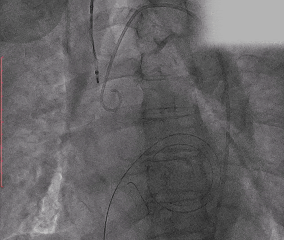

Step 4. 行PBMV术治疗

Step 5. 主动脉瓣定位及释放